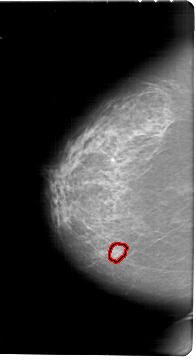

A_1789_1.LEFT_CC

LEFT_CC LINES 6871 PIXELS_PER_LINE 3706 BITS_PER_PIXEL 12 RESOLUTION 43.5 OVERLAY

FILE: A_1789_1.LEFT_CC.OVERLAY

TOTAL_ABNORMALITIES 1

ABNORMALITY 1

LESION_TYPE MASS SHAPE LOBULATED MARGINS OBSCURED

ASSESSMENT 4

SUBTLETY 3

PATHOLOGY BENIGN

TOTAL_OUTLINES 1

BOUNDARY